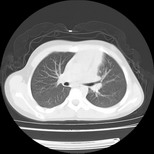

女,12岁,前期发热,咳嗽,无痰,经头孢抗炎无效。ct右肺上叶实变影.5天后公布病理结果。以下是2010-2-13ct片

经过胸部穿刺活检为支原体感染。以下示抗支原体感染30天后所见,病灶明显缩小,临床症状消失: